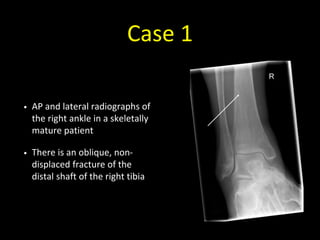

Case 1

• 30 year old with pain in the right ankle after a fall

• AP and lateral radiographs of

the right ankle in a skeletally

mature patient

• There is an oblique, non-

displaced fracture of the

distal shaft of the right tibia